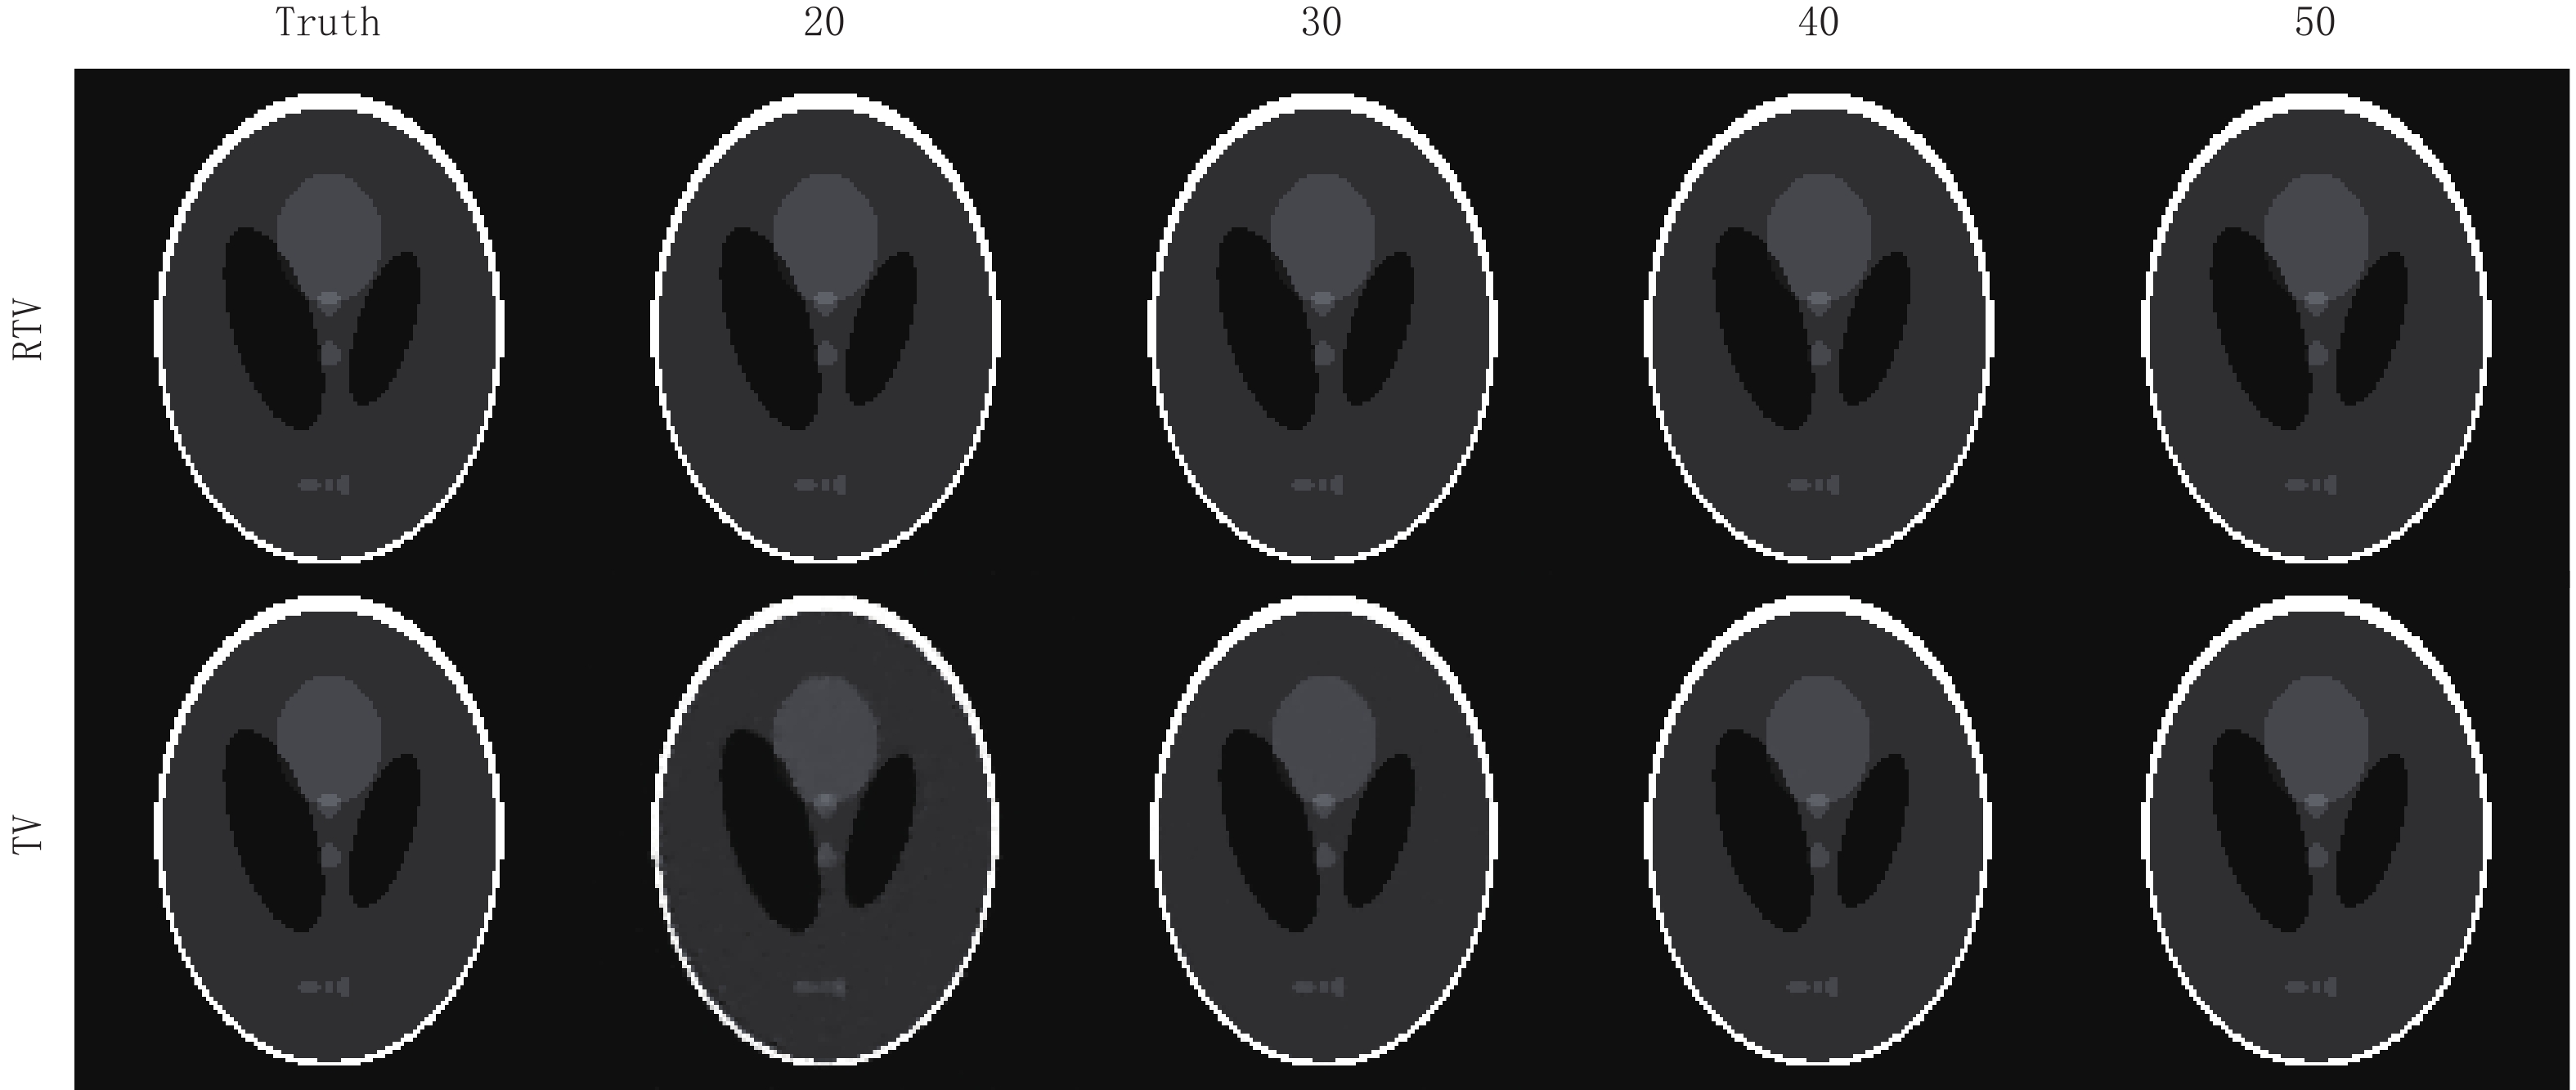

3.2 算法稀疏重建能力的评估与正则项各参数的选取

为了评估RTV算法的稀疏重建能力,本节实验分别使用RTV算法和TV算法对FORBILD、Shepp-Logan和真实CT图像模体在20,30,40,50个投影角度下进行模拟实验。这些模体的大小都是128

$ \times $ 128。在实验分析中,使用均方根误差(RMSE)和结构相似性(structural similarity,SSIM)作为图像重建质量的度量。在文献[2]对ASD-POCS算法的阐述中,数据容差

图8显示了两种算法关于Shepp-Logan模体的重建结果,通过对比,可见在20个投影角度下,RTV最小化重建算法的重建结果与原图相比用肉眼几乎看不出与原图的区别。而TV最小化算法在20个投影角度下的重建结果对于图像结构的保护还是有所欠缺,模糊了较多的细节。但随着投影角度的增加,其重建精度也越来越高,两种算法的重建结果与原图相比都几乎一样。

图6中的(b)图显示了Shepp-Logan模体在20个投影角度下使用RTV和TV最小化重建算法的RMSE趋势曲线的比较,显然,RTV最小化重建算法经过500次迭代达到收敛点后拥有更高的重建精度,其最终的收敛精度是8.010×10-5。而TV算法最终的收敛精度只有1610×10-5。

表2比较了使用RTV算法和TV最小化算法在20到50个投影角度下重建Shepp-Logan模体的RMSE和SSIM的比较,可见在Shepp-Logan模体上的重建,RTV最小化重建算法同样具有更高的的重建精度和结构相似性。